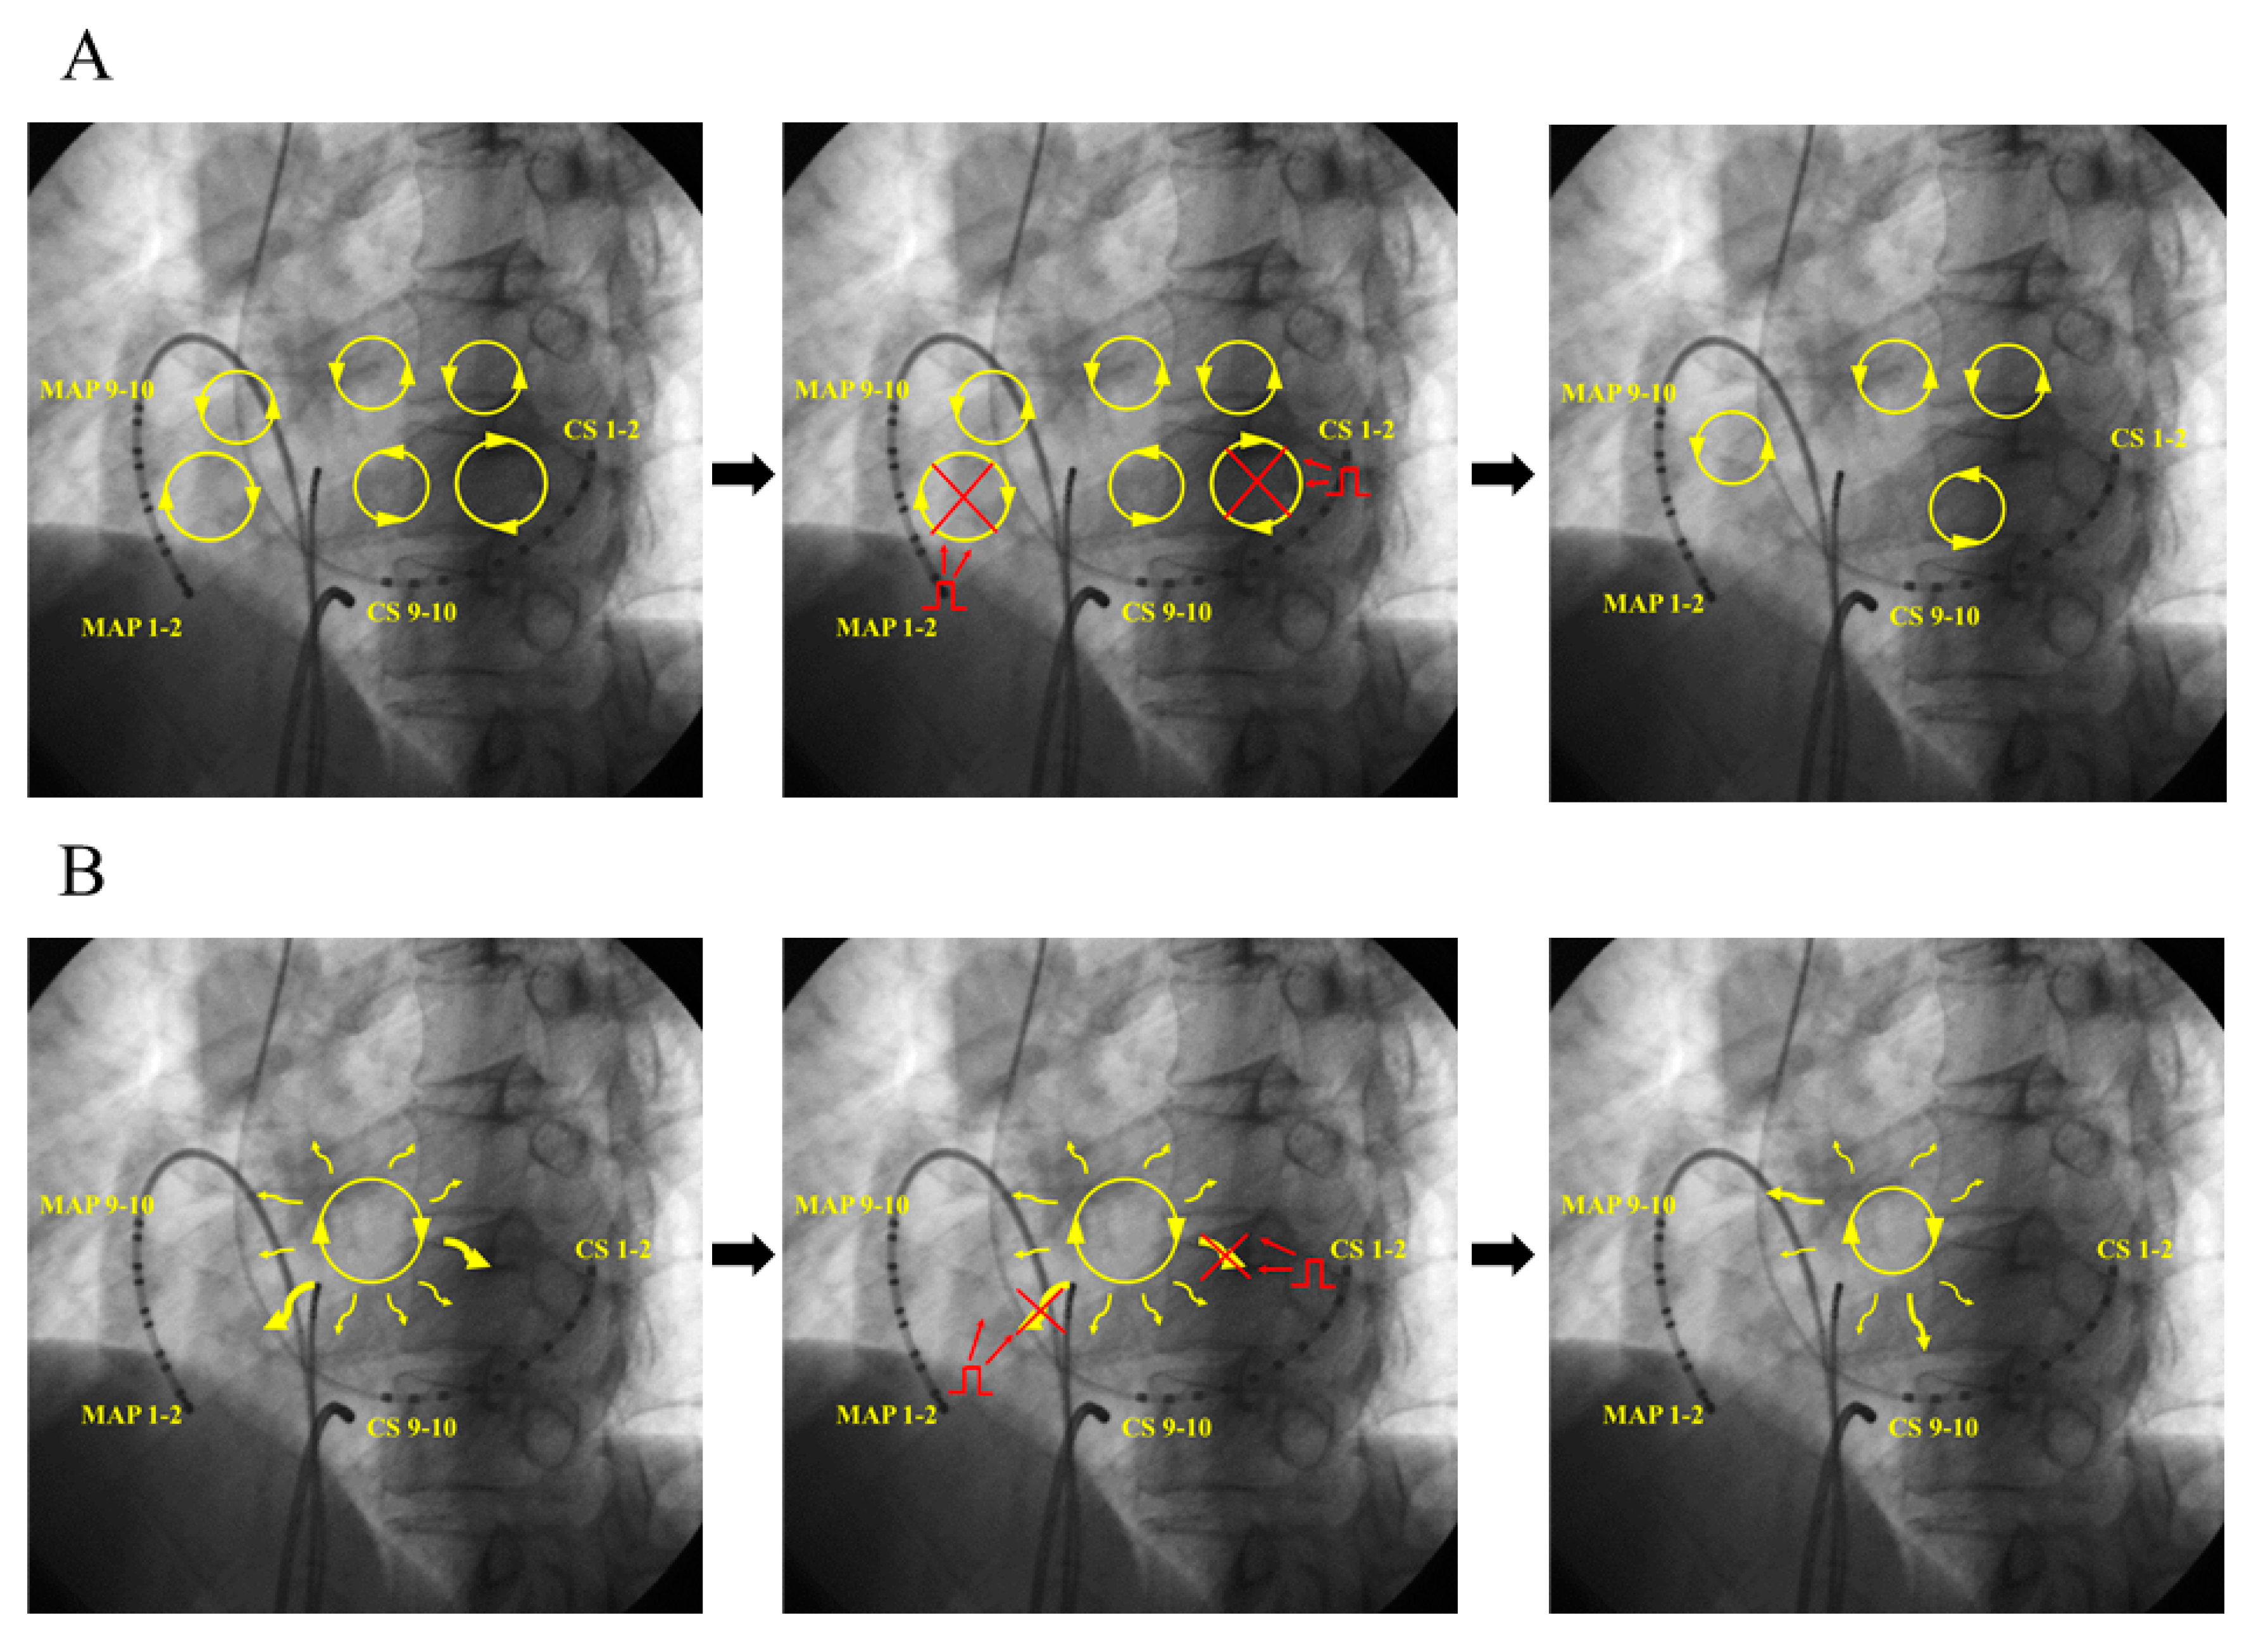

4.1. Mechanism of AF Termination

- (A)

- (B)

- (C)

- Leading circle theory [14]; The presence of an excitable gap is well known for the maintenance of AF. Pacing stimuli entrain and fill the excitable gaps of tachycardia, affecting the refractory period. Eventually, AF is unable to sustain itself and thus terminates slowly.